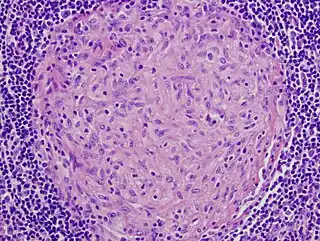

![]() Imagen microscópica de un granuloma (sin necrosis) en ganglio linfático. H-E. | ||

Aunque en ocasiones el término granuloma se utiliza genéricamente para designar "pequeños nódulos" que pueden abarcar desde nevus a tumores, la utilización correcta es la que se hace en patología, siendo una agrupación organizada de macrófagos,[4] donde estas células suelen estar tan cercanas entre sí, que los bordes de las células individuales son difíciles de apreciar formando una estructura cerrada, de bola. Las agrupaciones de macrófagos dispersos no son considerados como granulomas.

Al fracasar la fagocitosis del cuerpo extraño, se produce una activación de linfocitos T, que a su vez activan a los macrófagos o histiocitos que son los componentes principales del granuloma. A menudo, aunque no siempre, se fusionan para formar células gigantes multinucleadas.[5] A estos macrófagos que forman el granuloma se les suele denominar "epitelioides", debido a su cierto parecido con las células epiteliales. Estos se diferencian de los macrófagos normales en que poseen un núcleo mayor y alargado, además de presentar una coloración más eosinófila cuando se tiñe con eosina. Todos los granulomas, independientemente de la causa, pueden contener células adicionales y una matriz, como linfocitos, neutrófilos, eosinófilos, células gigantes multinucleadas, fibroblastos y colágeno (en fibrosis, típica de la sarcoidosis) y estar rodeados por leucocitos mononucleares, sobre todo linfocitos y en ocasiones células plasmáticas. Las células adicionales son a veces una pista de la etiología del granuloma.

Una característica importante de los granulomas es si contienen o no necrosis. La necrosis se refiere a células muertas que, bajo el microscopio, aparecen como una masa de escombros sin forma, sin presentar núcleos. Un término relacionado, "caseificación" (literalmente: convertir en queso) se refiere a una forma de necrosis que, a simple vista (es decir, sin un microscopio), parece similar al queso ("caseosa"), y por lo general (pero no únicamente) una característica de los granulomas de la tuberculosis. La identificación de la necrosis en los granulomas es importante porque granulomas con necrosis suelen tener causas infecciosas. Hay varias excepciones a esta regla general, pero no deja de ser útil para el día a día de los diagnósticos.